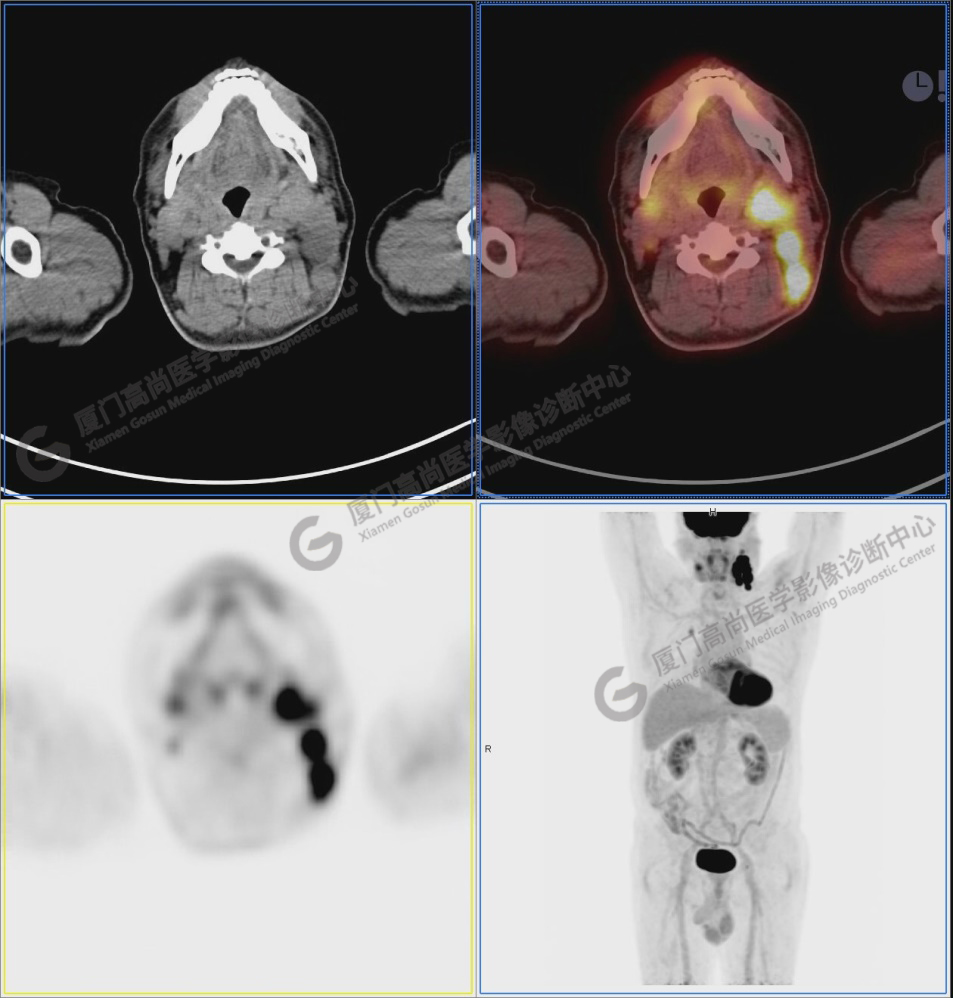

圖2:雙側(cè)頸部多發(fā)增大淋巴結(jié),代謝不同程度增高,考慮為轉(zhuǎn)移。

圖6-9:鼻咽左側(cè)壁增厚,代謝異常增高,考慮為鼻咽癌